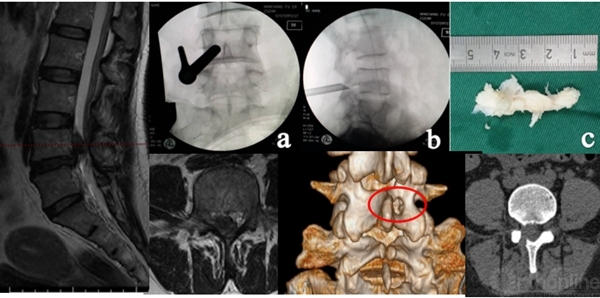

3D-CT:可观察骨性结构狭窄,如椎间孔区域狭窄,此类患者可行脊柱内镜下椎间孔扩大出口神经根减压治疗

3D-MRI:普通MRI无异常,3D-MRI发现游离髓核,行脊柱内镜取出游离髓核

3D-MRI:对一些特殊类型的椎间盘突出(如极外侧腰椎间盘突出)可起到更加准确的诊断作用

介入诊断技术:选择性神经根阻滞技术、椎间盘造影技术等,不仅可以从患者的主观感受进一步精准诊断,同时对脊柱内镜手术的疗效可以起到预测作用。

怀疑融合临近节段极外侧突出,选择性神经根阻滞术明确诊断